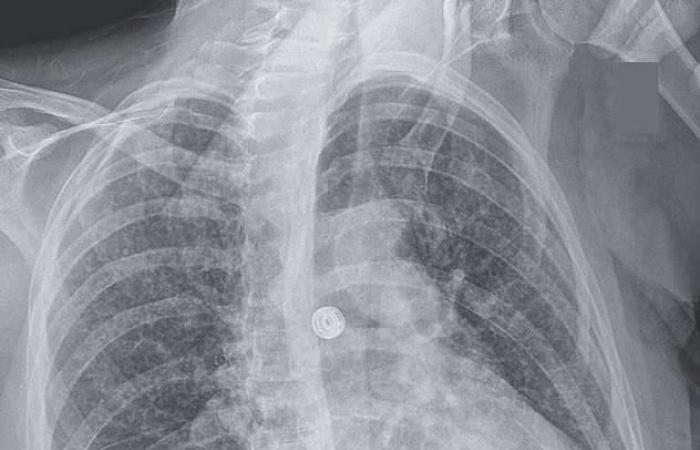

أظهرت الفحوص الشعاعية وجود عقيدات صغيرة منتشرة في الرئتين، إلى جانب آفات في الكبد والغدد اللمفاوية والبنكرياس والدماغ. وبعد 9 أسابيع، أكدت التحاليل المخبرية إصابتها ببكتيريا المتفطرة السلية المسببة لمرض السل، في شكل نادر يعرف بالسل المنتشر الذي يصيب أعضاء متعددة من الجسم.